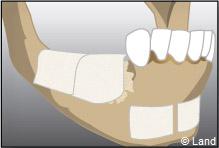

LES GREFFES D’APPOSITION

Elles sont indiquées dans les insuffisances d’épaisseur.

Les différentes étapes :

Prélèvement du greffon au niveau du site donneur

Apposition et stabilisation du greffon.

Recouvrement du greffon avec de l’os synthétique et une membrane

Après 6 mois de cicatrisation, il est possible de poser les implants qui recevront dans un deuxième temps les couronnes.